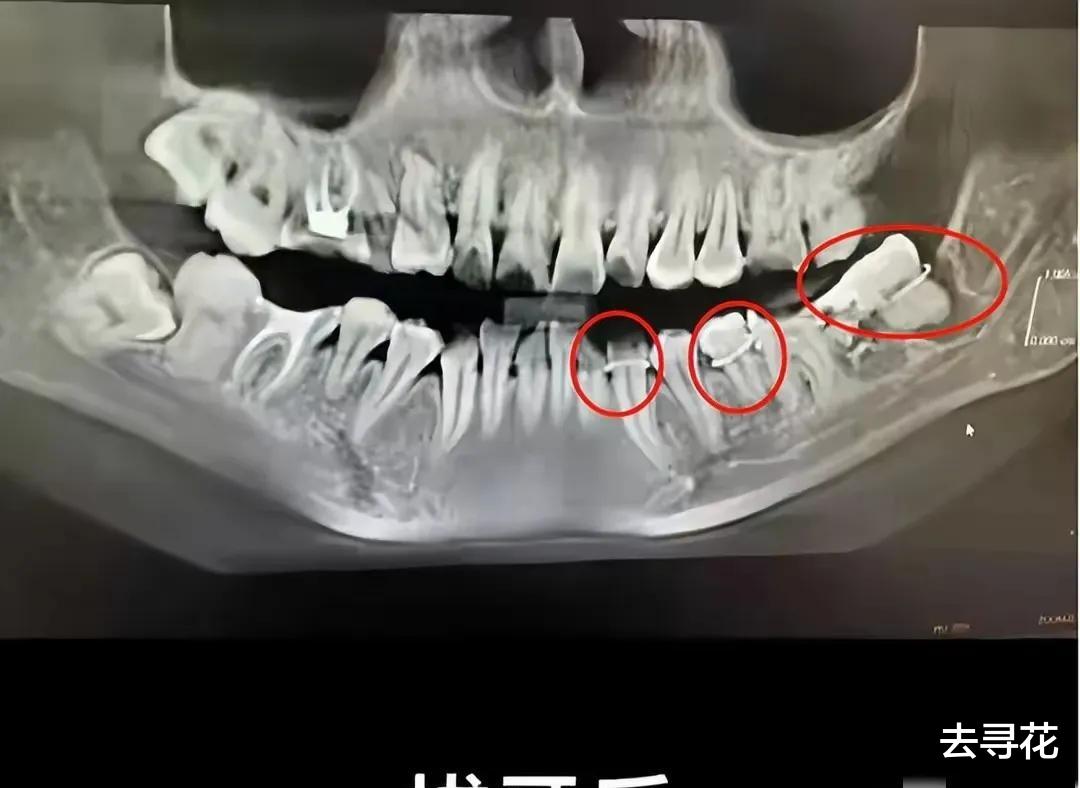

谁会想到,一次普通的拔牙,竟会酿成如此惨剧?吴芳芳的遭遇,让我们不得不深思:究竟是什么样的无力感,压垮了这位母亲?是医生的失误?还是医院冷漠的态度?抑或是,整个社会都欠缺的那份关怀和保护?这颗错拔的牙,不仅带走了吴芳芳的生命,更带走了一个家庭的希望,这又该由谁来承担?

事件中,医院的处理方式,无疑是引发众怒的导火索。拔错牙本身就是医疗事故,而之后医院的敷衍、甚至可能存在的篡改病历,更是雪上加霜,将一个本就绝望的母亲推向了深渊。试想一下,在身心俱疲、遭受巨大委屈的情况下,一个弱势的患者,面对医院的强势和冷漠,是多么的无助和无力?我们常常说,医院是救死扶伤的地方,是守护健康的地方,可当它变得冰冷、冷漠,甚至充满欺瞒之时,又该如何让人相信它?